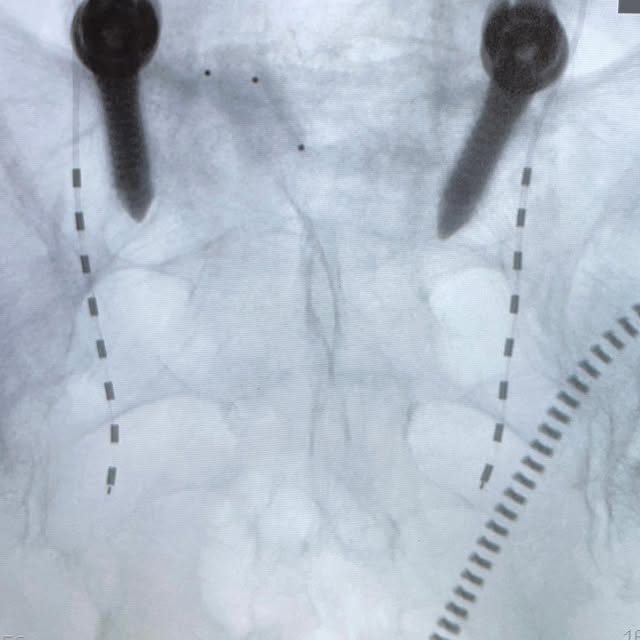

2023-10-21

This patient was crying with tears of joy after the implant of sacral nerve stimulator. Her urinary incontinence was so severe that she could not sleep at night for many years. Surgeries/medications/pelvic floor exercise failed to provide any significant relief. Trial of the device gave her 90% of relief. Daily leak went down from 25 times to 0, a life changing experience. In terms of the surgical anatomy, her sacral foramen were difficult to visualize on AP view due to the unusual anatomy. It was overcome with a very steep cephalad tilt to clearly reveal the foramen. #urinaryincontinence #urinarysystem #incontinence #incontinenceawareness #nerveandpain #interventionalneurology #sacralnervestimulation #axonics #lifechanging #neuromodulation